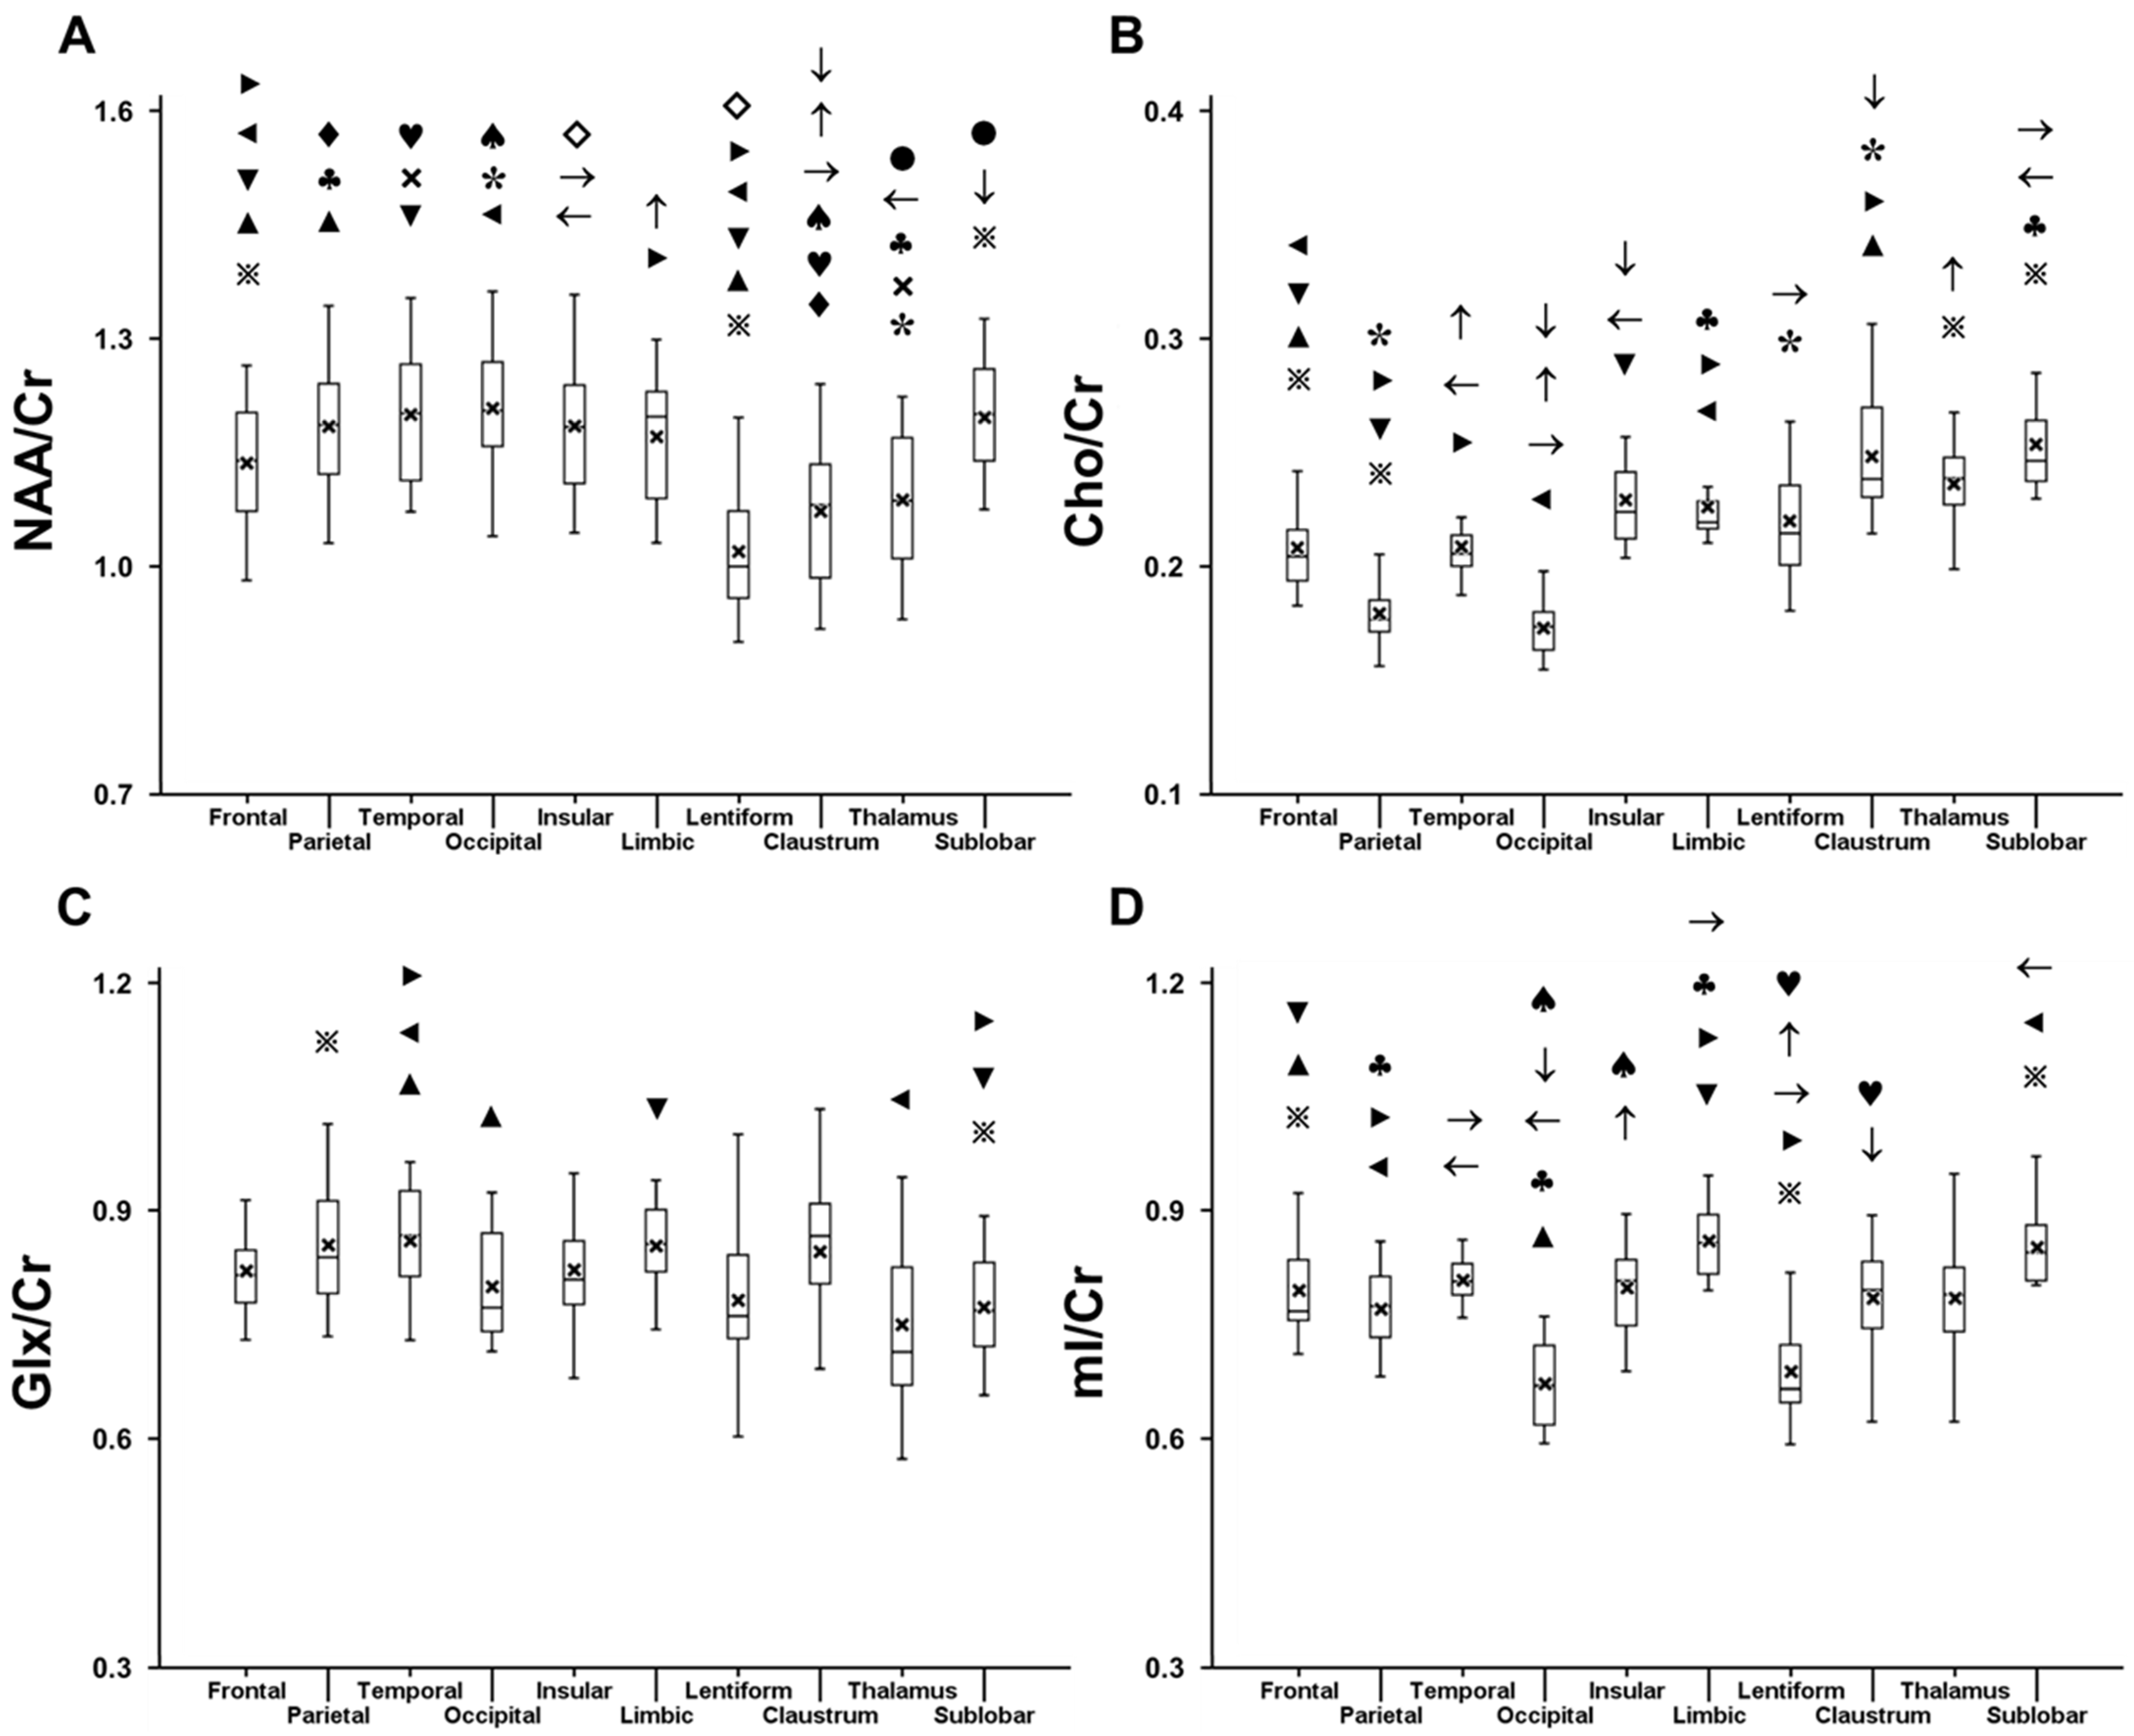

2.1. Variation in Metabolite Ratios with Anatomical Location

2.2. Laterality

2.3. Sex-Related Variation

2.4. Correlation with Age